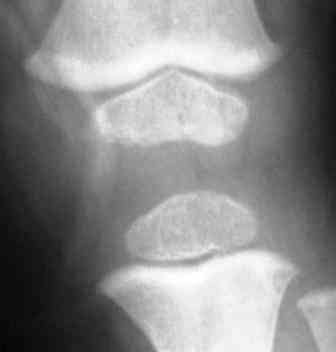

Уважаемые коллеги! Помогите уточнить диагноз. На ортопедический прием мама привела упитанного 3 летнего мальчика. Родился и рос нормальным ребенком. Последнее время стал жаловаться на ножки. Мама заметила Х-образную деформацию нижних конечностей. При осмотре отмечена легкая вальгусная деформация коленных суставов, плоскостопие. Предполагаю, что это МЭД - множественная эпифизарная дисплазия. Р-грамма прилагается. Какие варианты лечения?. С уважением Виктор

При более близком рассмотрении Рг создается впечатление неоднородности структуры зоны роста в латералных отделах дист. бедра при нормальной

структуре медиальной пластинки. Эпифизы, на мой взгляд, выглядят вполне симметричными и не измененными.

Уважаемый Евгений! Спасибо за обстоятельный совет. Обязательно сделаю КТ или МРТ. Неоднородность структуры зоны роста я, к сожалению, не заметил. По-моему, возникают ассоциации с механизмом развития избыточной антеверсии шейки бедра. Но, все-таки у меня остается впечатление «сжатости» метафизов, особенно бедра.

Для иллюстрации привожу пример из «Нормальной рентгеноанатомии костно-суставной системы детей». В. И. Садофьева. ЛЕНИНГРАД «МЕДИЦИНА» 1990

^^^^^^^^сурово ;) В любом случае одних снимков коленных суставов для такого вывода недостаточно. По снимкам- норма